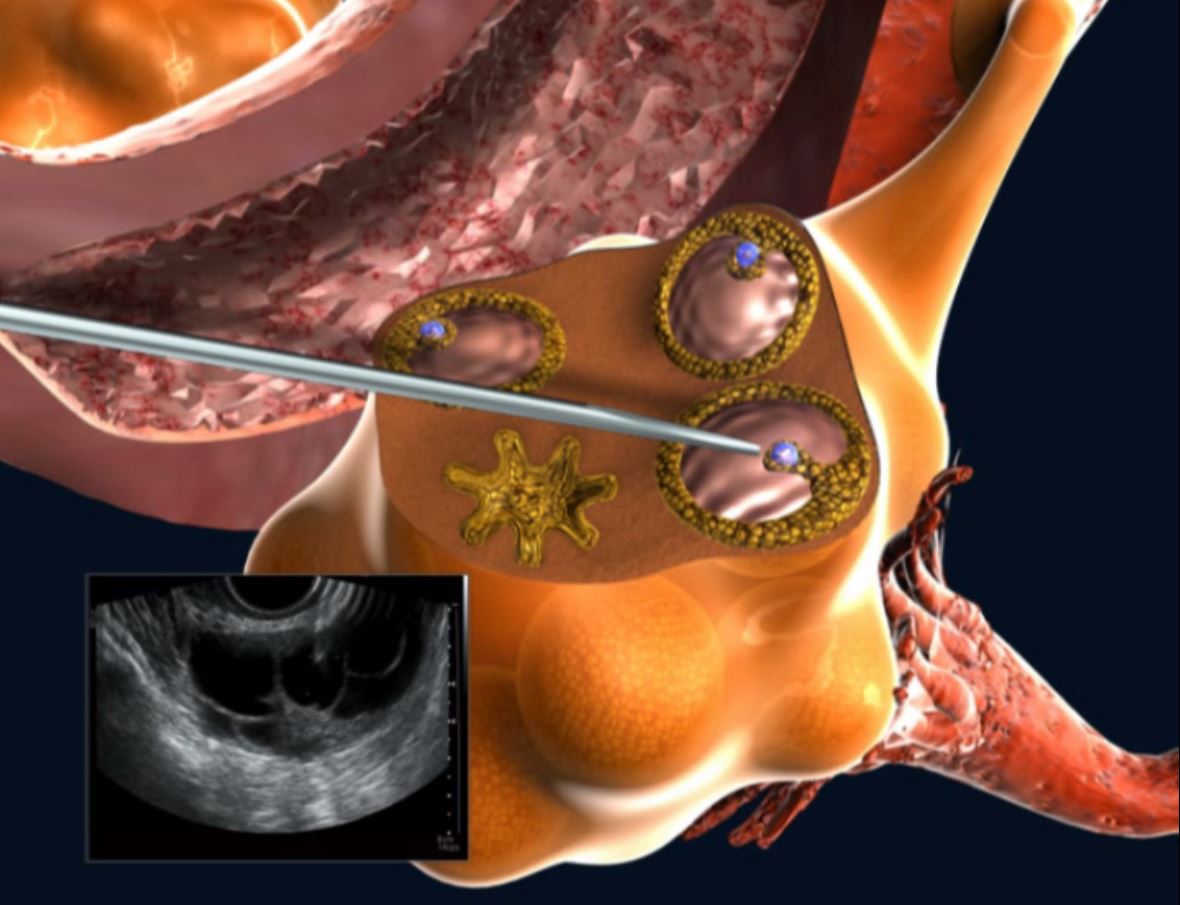

Созревание фолликула в яичнике: этапы и процессы